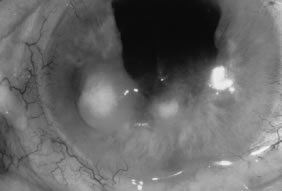

There is no distinguishing clinical sign by which to recognize the genus or species of the infectious filamentous fungus. F. solani is the most virulent organism and typically produces rapidly progressive infection characterized by epithelial and stromal ulceration, dense stromal necrosis, abundant cellular infiltrate, and edema in the adjacent stroma and hypopyon (Figs. 8 and 9). Delicate feathery components are transient. Individual hyphal fragments are rarely visualized. Infection by certain species of Aspergillus and Scedosporium (Figs. 10 and 11) resembles F. solani keratitis and progresses rapidly. Infection by less virulent organisms, such as Curvularia and Alternaria species, produces small, focal (less than 3-mm diameter) areas of nonnecrotizing stromal inflammation with delicate feathery borders (see Fig. 1 and Fig. 12). Macroscopic pigmentation may develop in keratitis caused by Alternaria, Curvularia, and other dematiaceous fungi (Fig. 13).4,11,14 The central component may progress to dense, opaque, gray-white suppuration in the deep stroma without enlargement in total area and may be accompanied by mild inflammation in the adjacent stroma. Iritis is minimal to moderate. Infection caused by other, relatively less virulent organisms resembles herpes simplex or noninfectious keratitis (Fig. 14).

Fig. 10. Scedosporium apiospermum keratitis in a 53-year-old woman, 10 days following unknown foreign body injury while gardening. Epithelial and stromal ulceration, endothelial plaque, and hypopyon. Note the corneal edema surrounding the central area of suppuration.

Fig. 11. Scedosporium apiospermum keratitis. Note the dense, suppurative stromal keratitis and hypopyon.